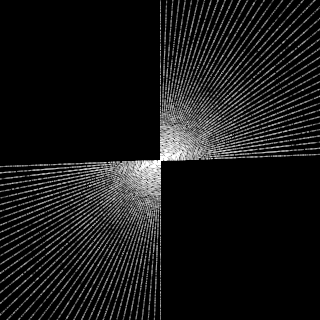

This article presents a novel undersampled magnetic resonance imaging (MRI) technique that leverages the concept of Neural Radiance Field (NeRF). With radial undersampling, the corresponding imaging problem can be reformulated into an image modeling task from sparse-view rendered data; therefore, a high dimensional MR image is obtainable from undersampled $k$-space data by taking advantage of implicit neural representation. A multi-layer perceptron, which is designed to output an image intensity from a spatial coordinate, learns the MR physics-driven rendering relation between given measurement data and desired image. Effective undersampling strategies for high-quality neural representation are investigated. The proposed method serves two benefits: (i) The learning is based fully on single undersampled $k$-space data, not a bunch of measured data and target image sets. It can be used potentially for diagnostic MR imaging, such as fetal MRI, where data acquisition is relatively rare or limited against diversity of clinical images while undersampled reconstruction is highly demanded. (ii) A reconstructed MR image is a scan-specific representation highly adaptive to the given $k$-space measurement. Numerous experiments validate the feasibility and capability of the proposed approach.